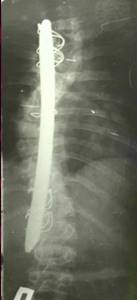

До сих пор в ортопедии принято множество методик измерения угла искривления позвоночника, и, соответственно, множество различных классификаций с разными величинами углов в градусах. Измеряется искривление так: на рентгенограмме надо провести несколько прямых линий между позвонками, а затем измерить углы между ними. В нашей стране наиболее распространена классификация, предложенная В.Д. Чаклиным. В иностранных научных источниках чаще приводится метод Дж. Кобба. Суть его заключается в следующем: на рентгеновском снимке позвоночника врач измеряет S-образное двойное искривление. В верхнем участке искривления с помощью линейки проводят две горизонтальные линии: одна над верхним позвонком, от которого идет кривизна, другая - над нижним. Если провести еще две линии, идущие перпендикулярно первым, образуется угол. Его и измеряют в градусах

Как видно, принцип измерения как у русского, так и американского профессора практически одинаковый. Разница в том, что по Чаклину, чем больше градусов, тем легче степень болезни, а по Коббу - наоборот.

Классификация выраженности сколиоза по В.Д. Чаклину (слева), по Лж. Коббу (справа) Степени тяжести сколиоза (углы искривления позвоночника, в градусах) Графический расчет на рентгенограмме: а - I степень; б - II степень; в - III степень; г - IV степень.

| По В.Д. Чаклину | По Дж. Коббу |

| I степень 180 - 175 | меньше 15 |

| II степень 175-155 | 20-40 |

| III степень 155-100 | 40-60 |

| IV степень меньше 100 | больше 60 |